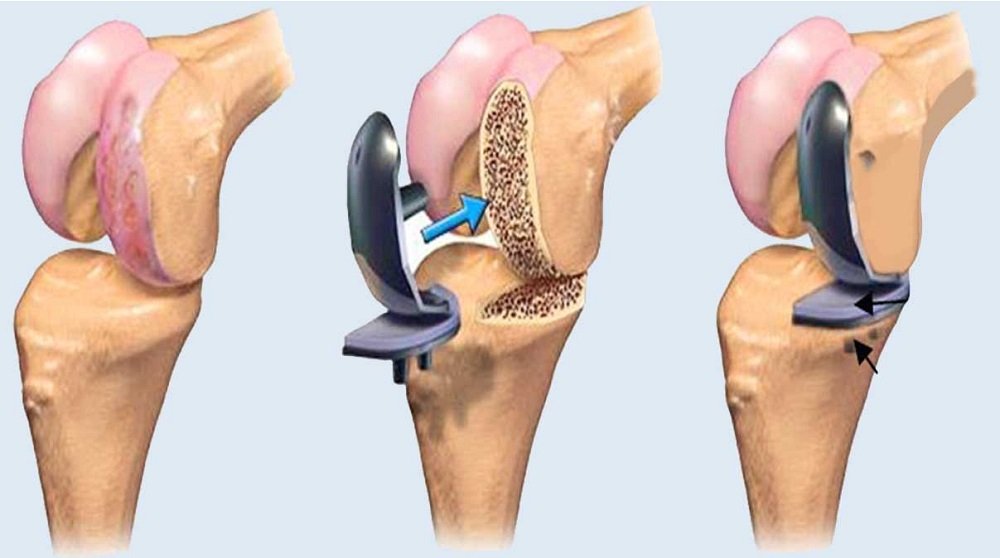

How to Prepare for Orthopedic Surgery: A Patient’s Guide

If your doctor has recommended orthopedic surgery, you may feel nervous. Proper preparation can help ensure a smooth surgery and faster recovery. Steps to Prepare Post-Surgery Care Conclusion With the right preparation and guidance, orthopedic surgery